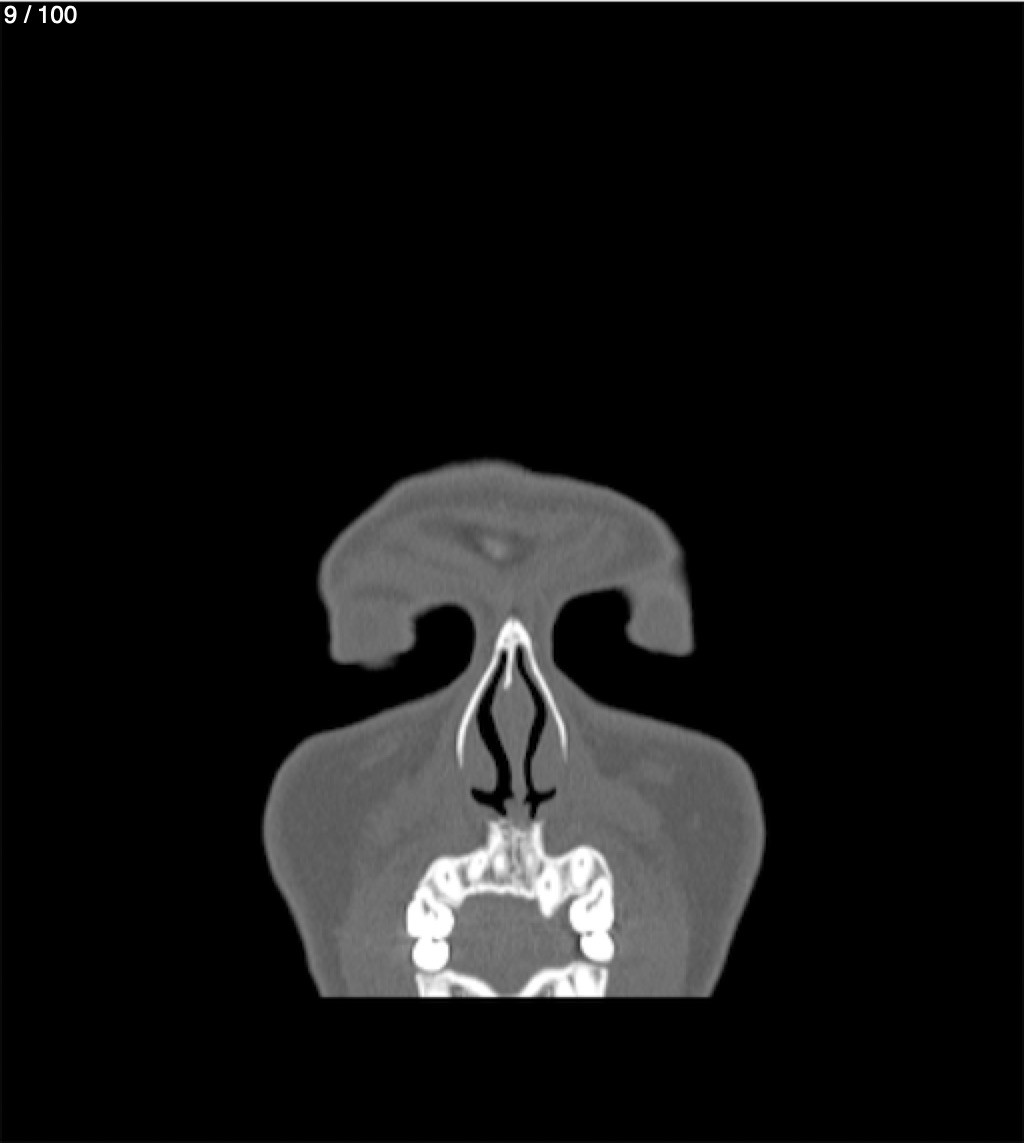

Yonelly Barrios Diaz 35A - T.C Craneo